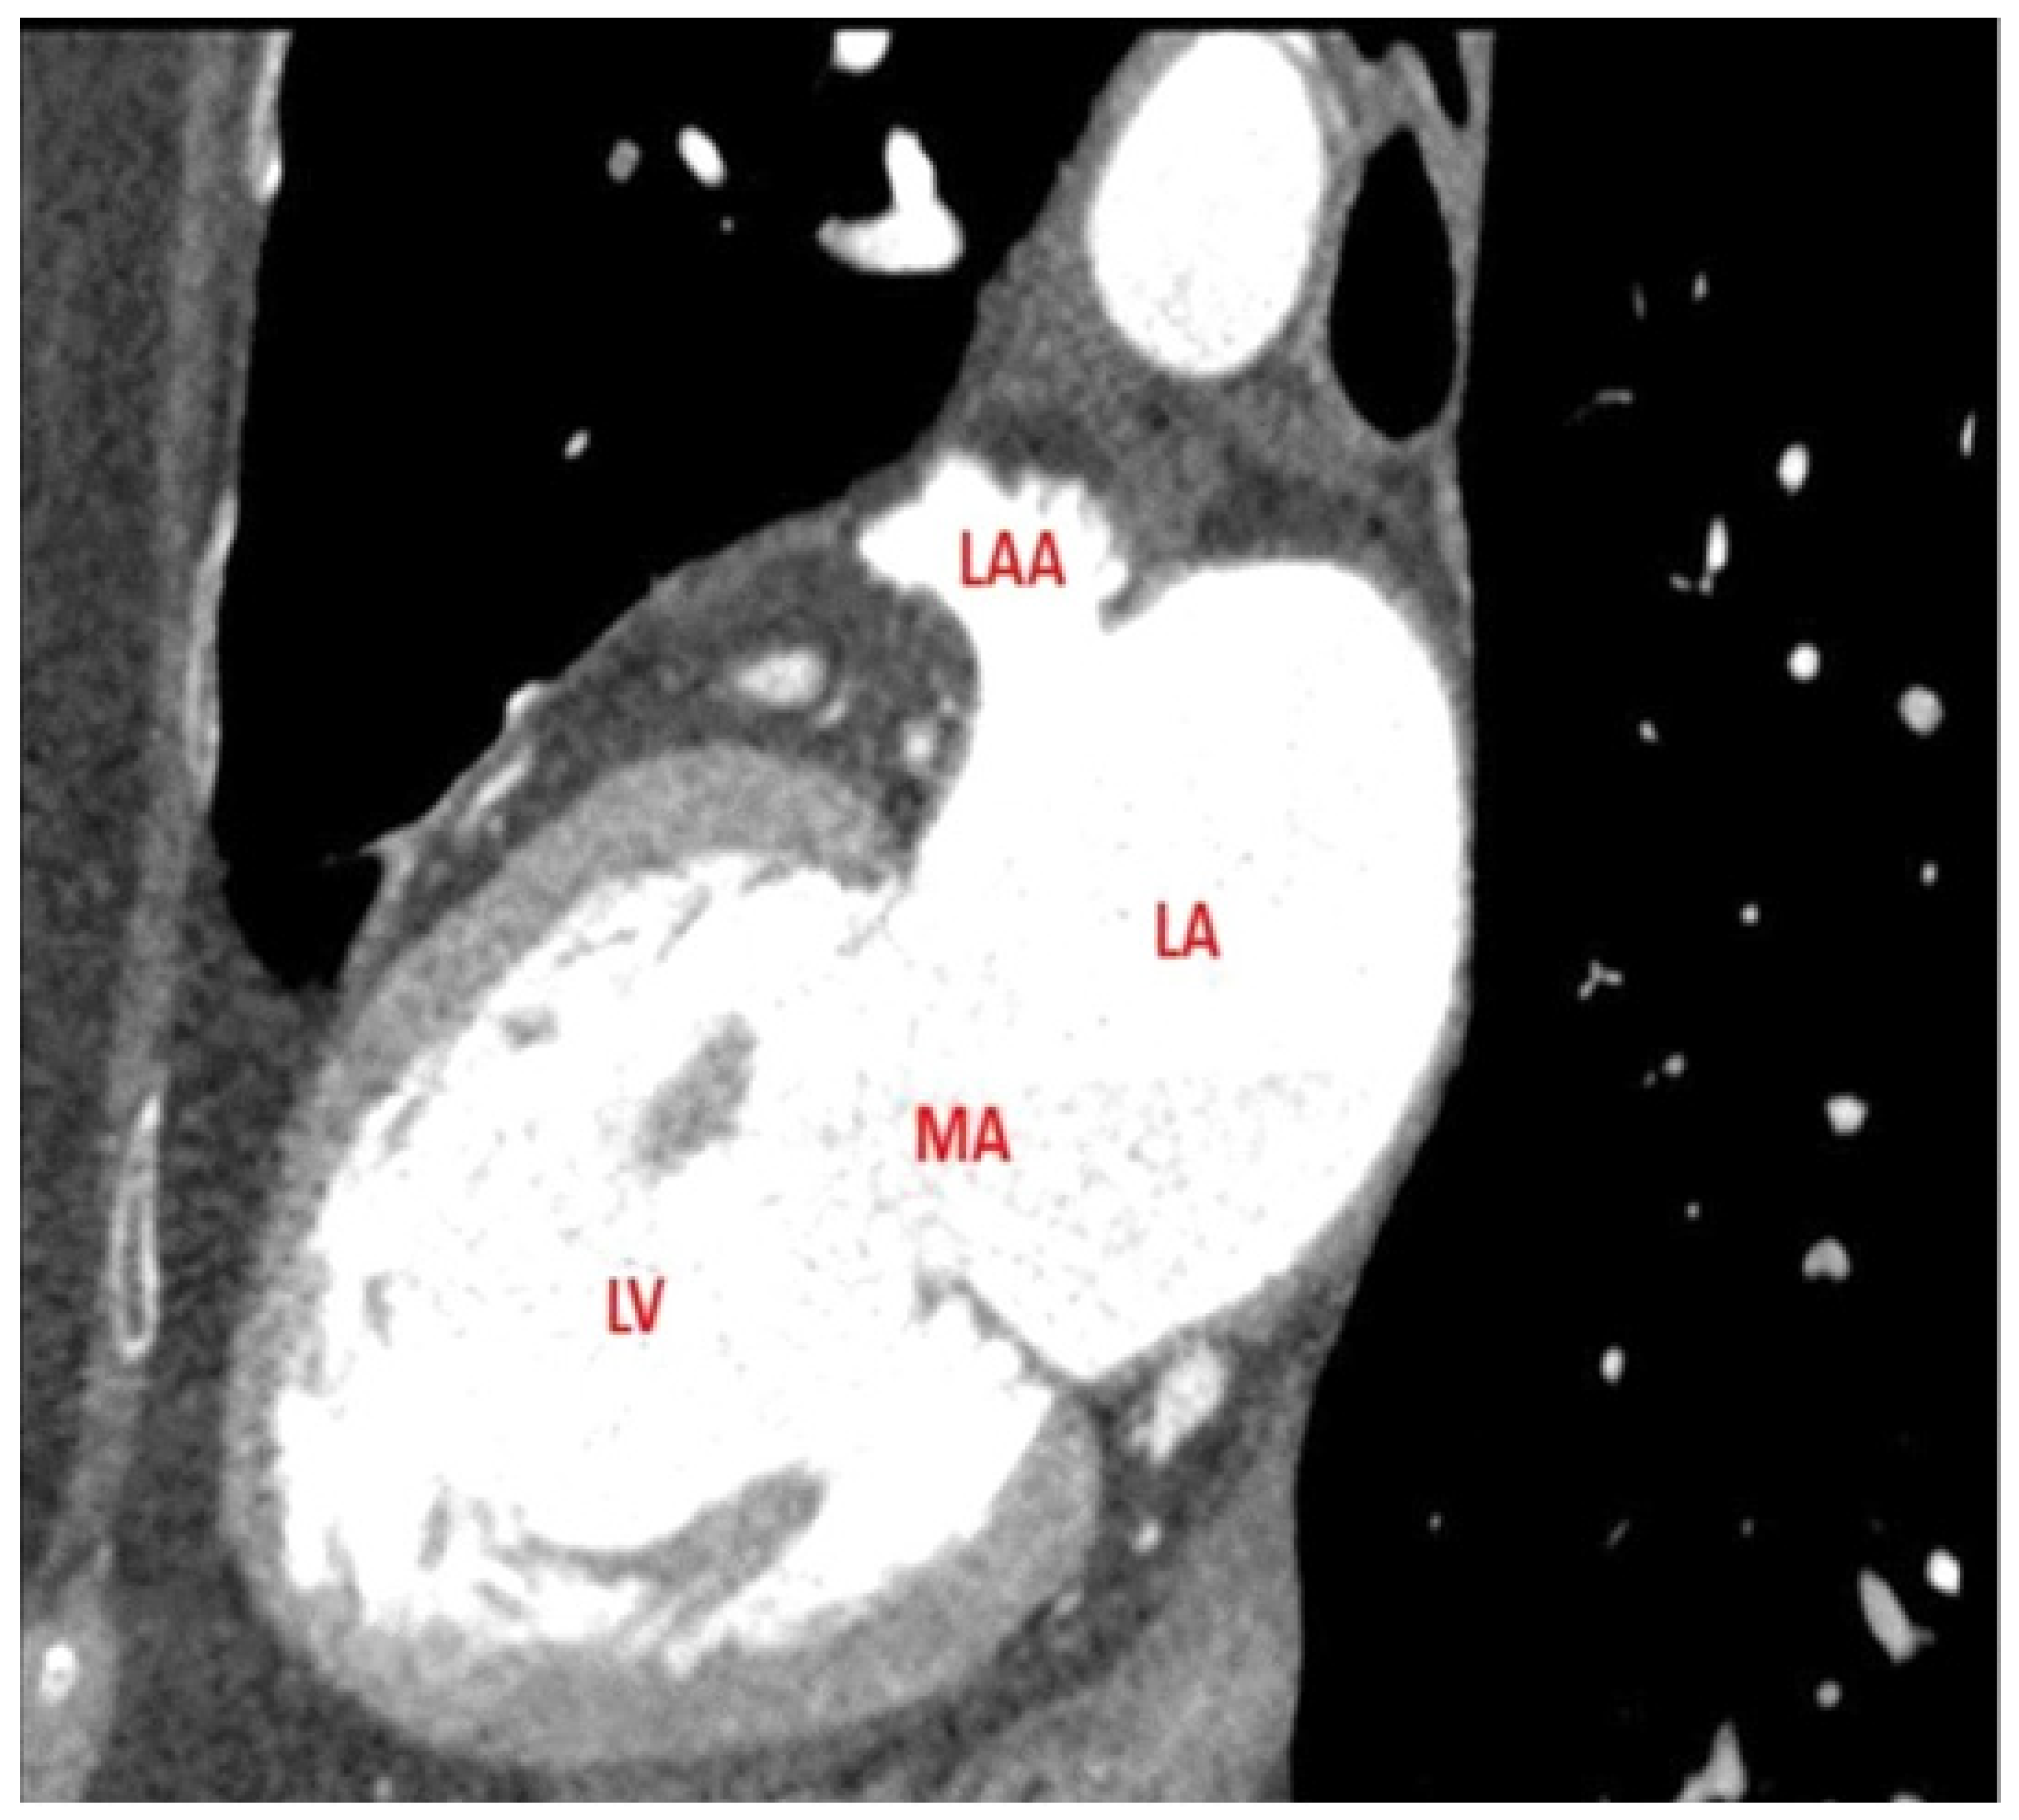

Cardiac Tomography and Cardiac Magnetic Resonance to Predict the Absence of Intracardiac Thrombus in Anticoagulated Patients Undergoing Atrial Fibrillation Ablation

2. Methods

2.2. Imaging Protocols